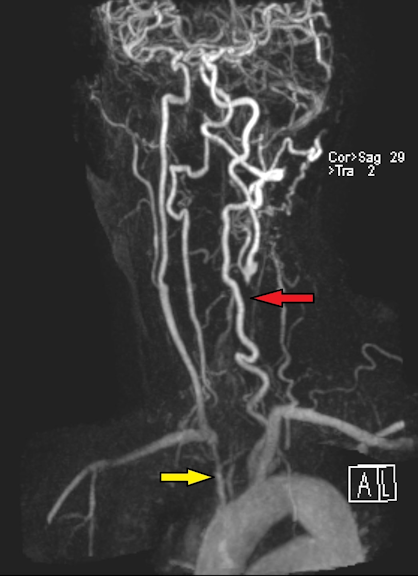

The patient received pan-retinal photocoagulation (PRP) in the right eye. Due to low tolerance, a retrobulbar block without epinephrine was administered to the right eye prior to the second PRP ten days later at which time 3,625 spots with a duration of 20 milliseconds of 500 mW were delivered using the indirect laser ophthalmoscope. Eighteen days after this laser session visual acuity had dropped significantly in the right eye to count fingers at 3’ with APD and attenuated posterior vasculature consistent with central retinal artery occlusion. MRA Extracranial showed proximal occlusion of aortic arch branches (Figure 4 [Fig. 4]). Due to concern for diminished blood supply from the aortic arch, the patient received a left subclavian artery to right common carotid artery bypass graft. One month after surgery, neovascular glaucoma developed in the right eye with intraocular pressure of 34 mmHg and 22 mmHg in the left eye. Pressures remained stable on Combigan twice daily. We treated the left eye with short sessions of laser for a total of 2,200 burns (0.05–0.07 sec, 300 micron) using the Laser indirect system for one session and the Varia multicolor slit-lamp system for the remaining 5 sessions. Six months after the bypass surgery, she maintained a visual acuity of 20/50 in the left eye and intraocular pressure was 18 mmHg.

Figure 4: MRA extracranial showing severe narrowing of the origin of the right brachiocephalic artery (yellow arrow) and complete occlusion of the left common carotid artery with distal reconstitution of flow near the bifurcation (red arrow).